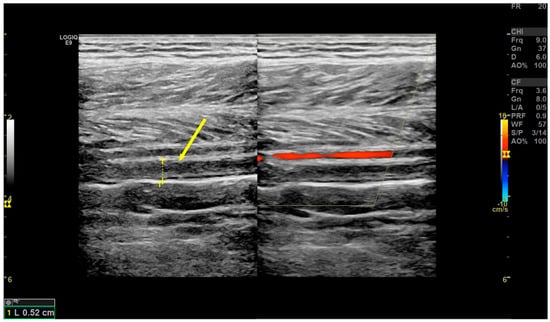

2.4. DVT Diagnosis

- Mantoni, M. Ultrasound of limb veins. Eur. Radiol. 2001, 11, 1557–1562. [Google Scholar] [CrossRef] [PubMed]